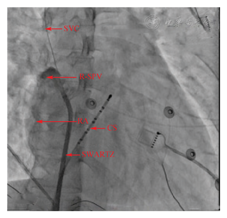

SVC:上腔静脉;R-SPV:右上肺静脉;RA:右心房;CS:冠状窦电极;SWARTS:房间隔。穿刺鞘穿刺房间隔后保留导丝右前斜30°进行右上肺静脉造影时,导丝进入上腔静脉,右心房、上腔静脉和右上肺静脉同时显影